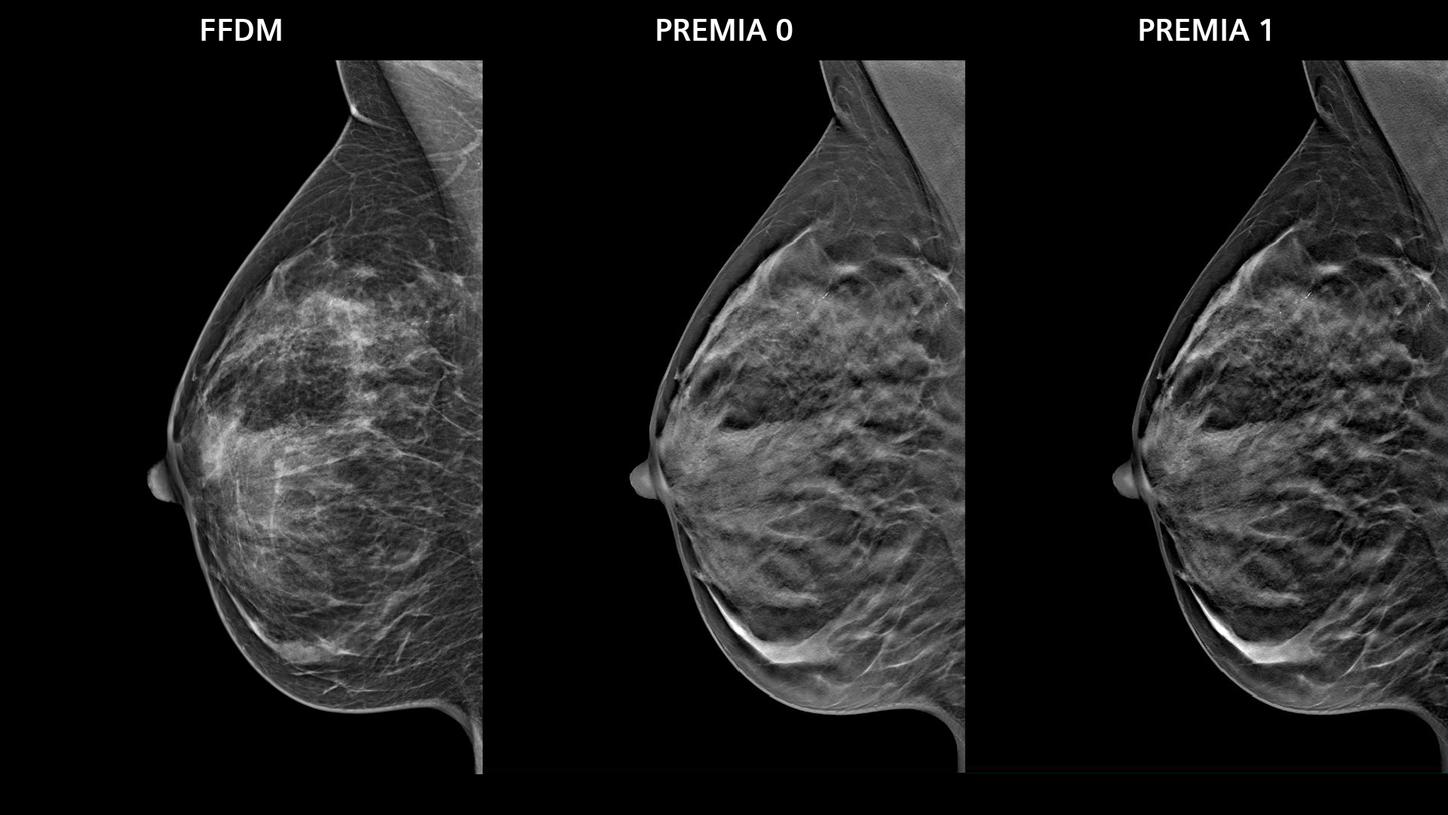

- PREMIA image reconstruction:

Improved image reconstruction framework- Reduce artifacts and enhance visibility of calcifications and lesions

- Comfortable transition from 2D and narrow-angle systems, thanks to customizable image impressions

- Boost synthetic mammogram sharpness, thanks to AI-powered noise reduction